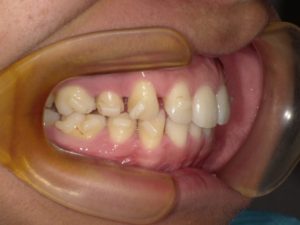

一番多いのは「歯を並べるスペースがないから」です。成人矯正の場合顎が成長済であるため、土台である顎の大きさはどうすることもできません。この顎が小さいことで歯がガタガタになってしまうという方も多くおり、このようなケースでは抜歯が「提要されることが多いのです。無理に並べてしまうと、前歯が突き出るような形ちょなり、歯並びがきれいでも口元が突出してしまうというケースも少なくありません。

八重歯の方は、外側に出た八重歯「犬歯」を抜くと思っている方も多くいらっしゃいますが、基本的には前から四番目の歯(第一小臼歯)を抜きます。その奥の歯(第二小臼歯)が虫歯になっていて、4番目の歯が健全だった場合には、虫歯の5番目の歯を抜いて健康な4番目を残すといったこともあります。